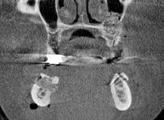

Målinger af pladsforholdene posteriort i en atrofisk mandibel

af processus alveolaris til canalis mandibulae på et CBCT-snit i det koronale plan (ca. 14 mm). C. Længdemål fra tværlinje (grøn), hvor bredden af processus alveolaris er 8 mm, til canalis mandibulae på samme CBCT-snit (ca. 5 mm).

Fig. 3. A. Vertical measurement from the top of the alveolar ridge to the mandibular canal in a CBCT section in the sagittal plane (approximately 13 mm). B. Vertical measurement from the top of the alveolar ridge to the mandibular canal in a CBCT section in the coronal plane (approximately 14 mm). C. Vertical measurement from horizontal line (green), where the width of the alveolar ridge is 8 mm, to the mandibular canal in the same CBCT section (approx. 5 mm).

Fig. 2. Fossa submandibularis (markeret med pile) ses oralt i den posteriore del af mandiblen på en 3-d-model i et softwareprogram til analyse af CBCTscanninger. Fig. 2. The submandibular fossa (marked with arrows) is located lingually in the posterior part of the mandible on a 3D model in a software program for analysis of CBCT scans. Fig. 3. A. Længdemål fra toppen af processus alveolaris til canalis mandibulae på et CBCT-snit i det sagittale plan (ca. 13 mm). B. Længdemål fra toppen